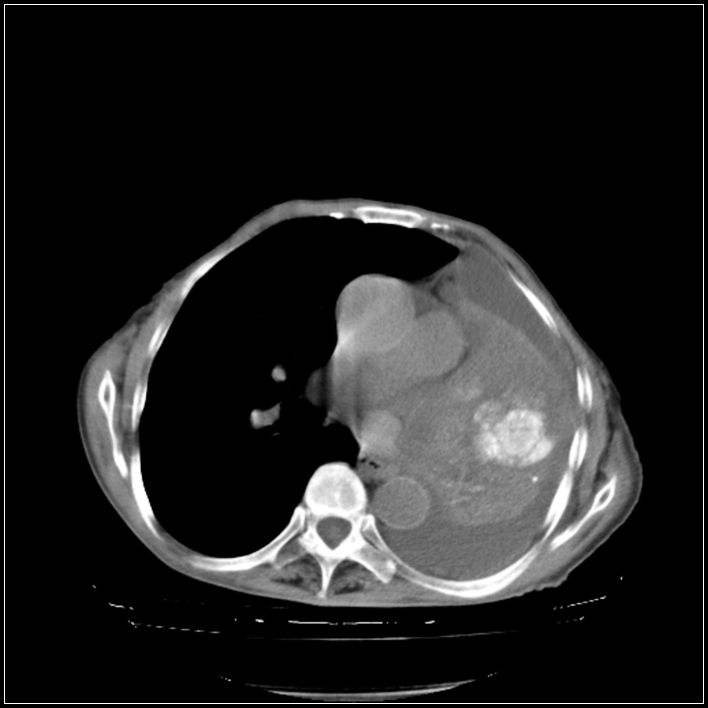

以下是引用影象小辈在2008-5-31 16:25:00的发言:[br]左侧胸腔团状不规则致密影,界欠规整,密度不均匀,其内可见更低密度影及高密度影,并可见包裹性胸腔积液 考虑为1.畸胎瘤 2.肺癌